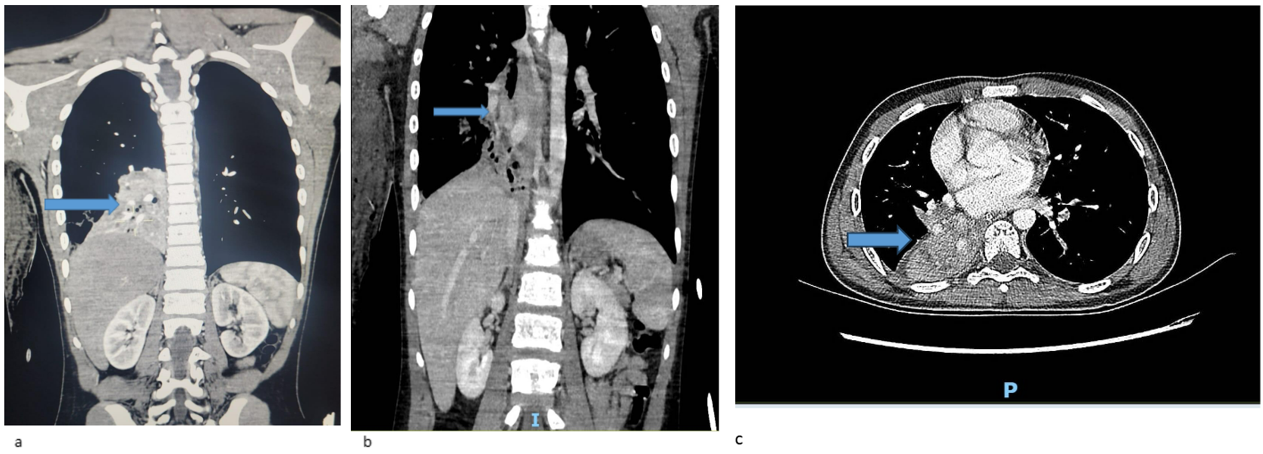

Following stabilization, flexible bronchoscopy revealed inflamed airways with a large obstructive clot in the right intermediate bronchus. As depicted in the Chest CT (Figure 1) demonstrated right lower lobe collapse with a "tree-in-bud" appearance, suggesting possible infection or hemorrhage. A CT angiogram raised suspicion of right lower lobe pulmonary sequestration (Figure 2).

Figure 1: Chest CT with contrast showing heterogeneous mass lesion in Right lower lobe of the lung, (a,b coronal views, c axial view).